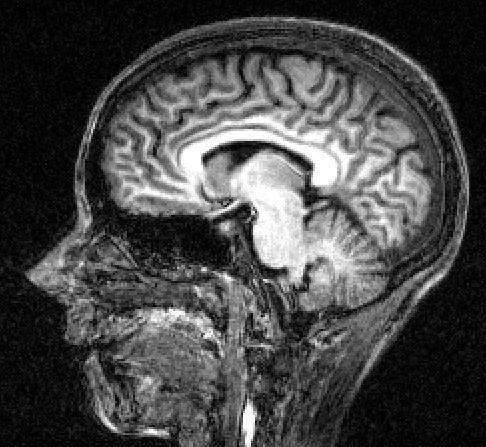

A picture of my brain. Even I can see there is no tumour there! Not as much grey matter as I would have hoped either. Hey ho